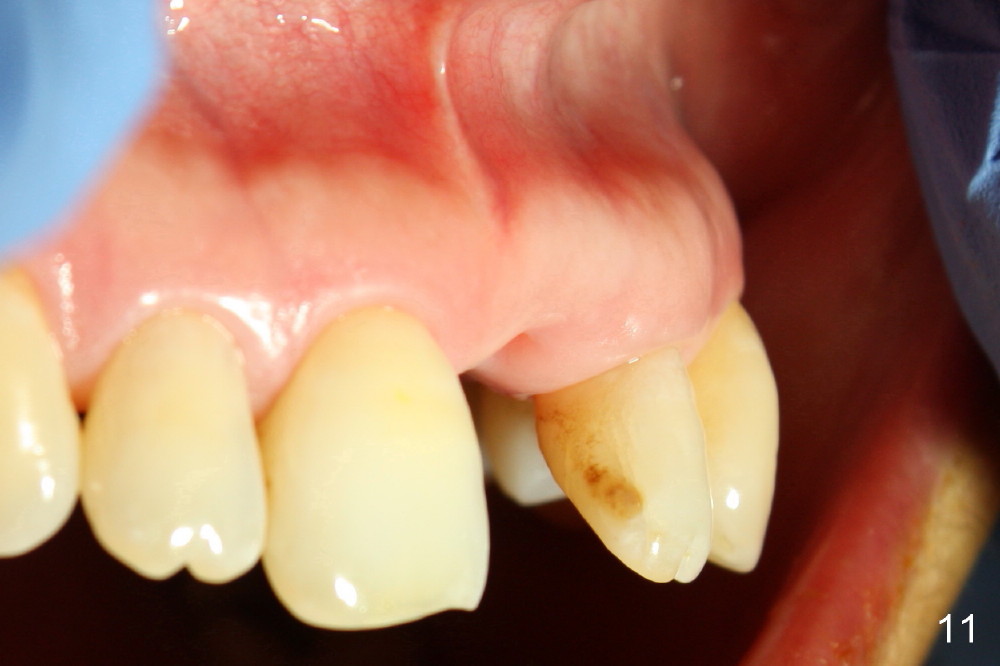

A 60-year-old lady had an abscess mesial to #9 six years ago (Fig.1,2 <), treated as a perio lesion by laser (Fig.3) and osseous surgery without bone graft (Fig.6, followed by CT exam revealing semi-circumferential bone loss (Fig.4,5). When the perio treatment failed, attention was paid to endo aspect (Fig.7-9). In fact the pulp was found to be vital when access to root canal therapy was made. As expected, the treatment failed again. The palatal fistula persisted. The infection was suspected to be a source of remote immediate implant site (#30). The tooth #9 was extracted. It appears that there is a semilunar crack line in the linguomesial root (Fig.12). When the socket healed 2 weeks post extraction (Fig.10), the #30 buccal defect was debrided with bone graft. There was no bone resorption 4 weeks post extraction (Fig.11); a 4.5x17 mm implant was placed (Fig.13-15). An immediate provisional was fabricated (Fig.16-18). Fig.19,20 were taken 3 months post implantation and 7 months post cementation, respectively. Dense bone forms around the implant coronally 4 years 5 months post cementation (Fig.21), while the gingiva is healthy palatally (Fig.22) and buccally (Fig.23).